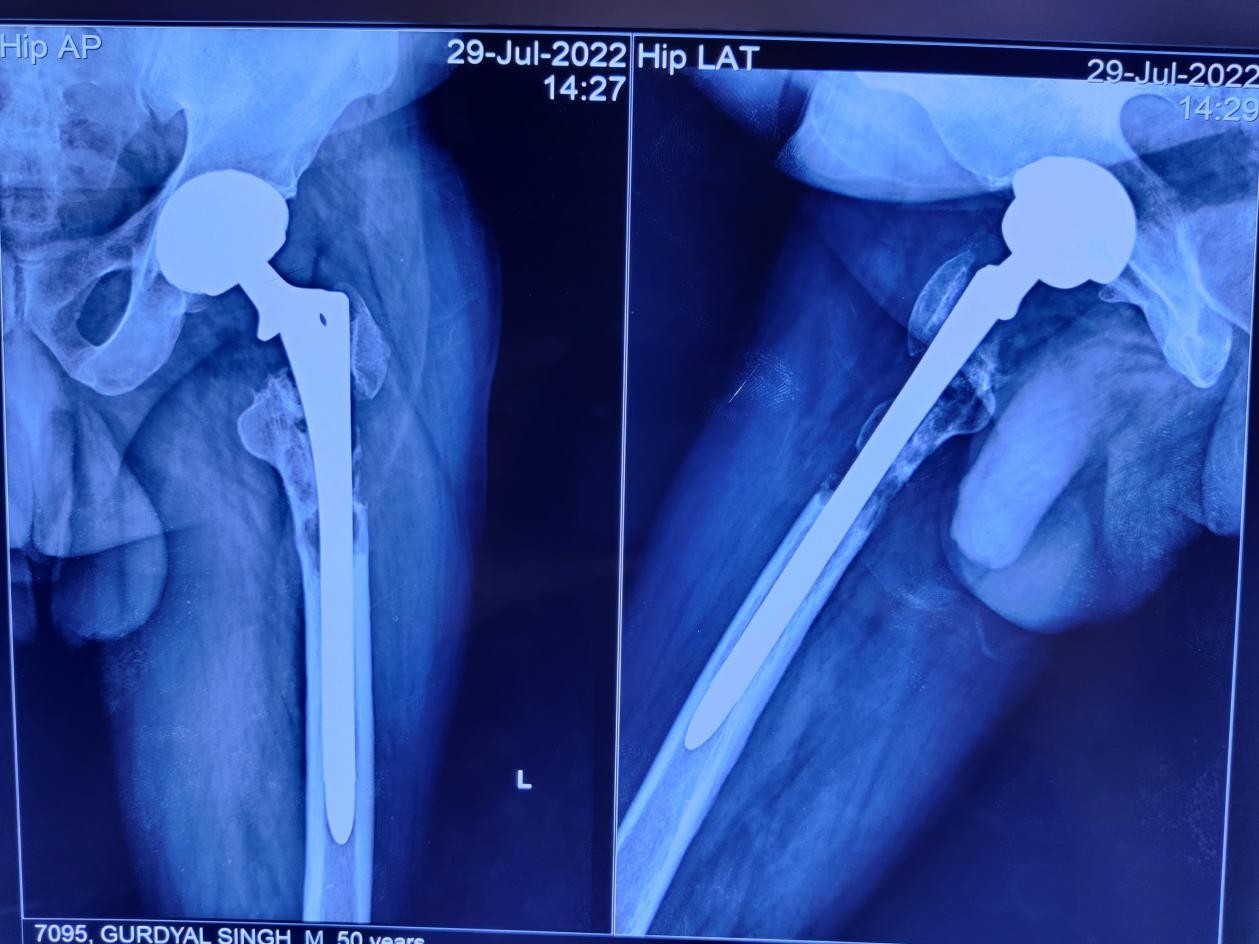

On clinical examination, he had two healed linear scars, one on the anterior proximal thigh of a size of 15 cm and another at the lateral aspect of 21 cm. There was diffuse tenderness on the left proximal thigh. There was no localized raised skin temperature, palpable swelling, and a discharged sinus. There was a true shortening of 1 cm in the left lower limb. There was no distal neurovascular deficit. A plain radiograph showed multiple lytic lesions around the proximal femoral stem 4 years following THA (Fig. 3). The magnetic resonance imaging (MRI) showed a peri-prosthetic T1 hypo and T2 hyper-intense lesion around the femoral stem with a T2 hypo-intense rim and areas of the cortical breach– likely pseudo-tumor. His erythrocyte sedimentation rate was 35 mm/h, and C-reactive protein was 28.6 mg/L. A bone scan revealed no evidence of any abnormal radio-tracer uptake in the body. Fluorine-2-fluoro-2-deoxy-d-glucose positron emission tomography/computerized tomography revealed a sclerotic lesion in the upper shaft of the left femur. The MRI of the brain and ultrasound of the kidney, ureter, and bladder were normal. Our initial differential diagnosis was sequelae of chronic osteomyelitis or pseudo-tumor. A core biopsy was done under fluoroscope guidance, which revealed the fragments of bone and surrounding fibro-collagenous tissue with features of LCH. The histiocytic cells were immuno-positive with S100 protein (focal), CD1a, and Langerin (focal) as depicted in Fig. 4. The patient started with chemotherapy-injectable Vinblastine 6 g/m2 I/V bolus once weekly and Tab.

Figure 3: Depicts the peri-prosthetic lytic lesion in the left proximal femur in the anterior-posterior and lateral view of the radiograph.